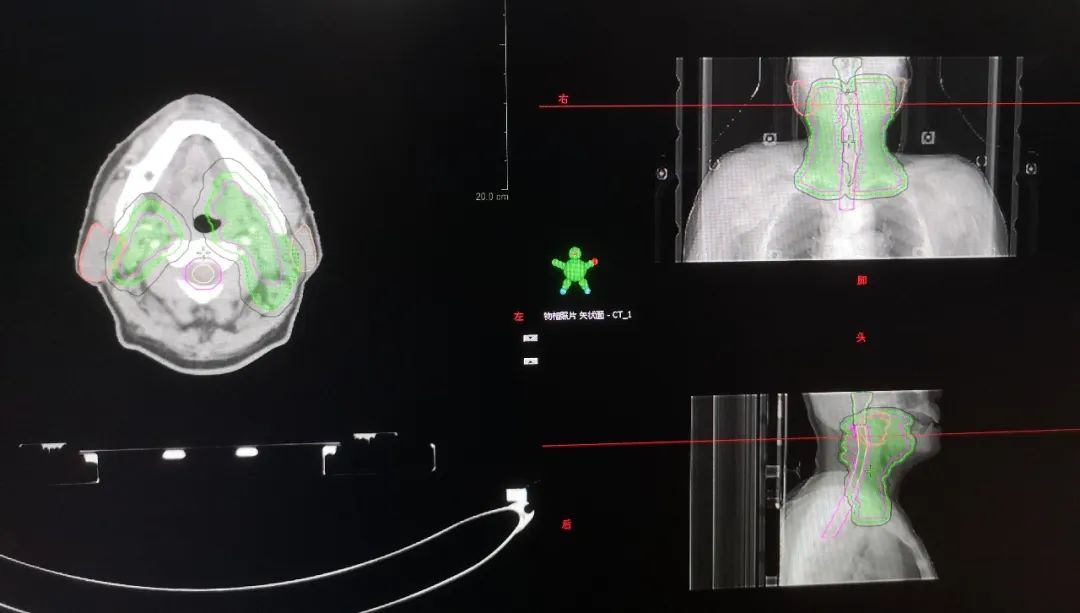

首先需要将定位的CT图像上传到放疗专用的计划系统里面。有时候对于特殊部位的肿瘤,为了更准确的显示病灶,除了CT图像以外,可能还需要用到MRI、PET等影像,将定位CT图像与MRI或PET/CT图像进行融合,这也是很耗时间的。有时候为了匹配更精准,可能需要连续几个小时的处理。这个步骤需要放疗物理师来完成的。

放疗物理师根据放疗申请单的要求,在专用的放疗计划系统里制定放疗计划,通过布野、设置各种各样的参数、优化、计算,从而实现放疗靶区达到处方剂量的要求,同时保护好周围的正常器官。制定一个好的放疗计划通常需要几小时几天时间不等,具体的时间由计划的复杂程度、放疗系统的优化速度、采用的何种放疗技术、工作人员的经验等多方面因素决定。比如,一个鼻咽癌的放疗计划,因为需要保护的危及器官太多,复杂程度远远高于一个全脑放疗计划,所用时间自然也会更多。一个放疗计划制定好以后,一般是要用这个计划给患者治疗整个疗程的,所以计划设计的重要性也就不言而喻了。